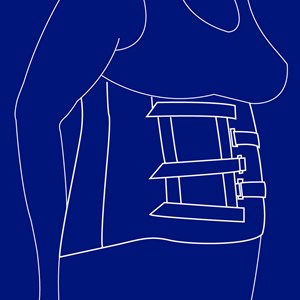

Abdominal korset

Type: pdf

Størrelse: 1129 KB